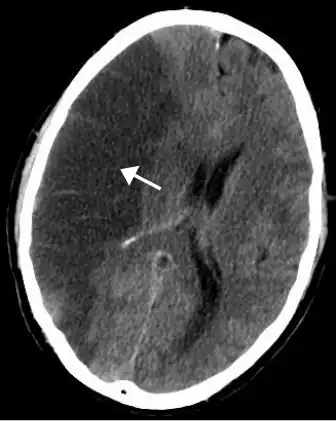

| A stroke of the middle cerebral artery can cause post-stroke depression | |